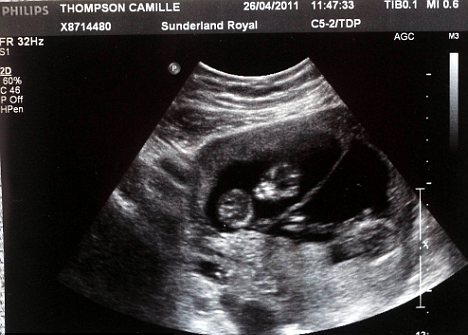

Ο Paul και Chamille Thompson την πρώτη φορά που πήγαν στο γιατρό ενημερώθηκαν ότι όλα πήγαιναν καλά. Στο δεύτερο υπέρηχο τους είπαν ότι η Chamille κυοφορούσε δίδυμα και… στον τρίτο ο αριθμός ανέβηκε στα τρία μωρά!